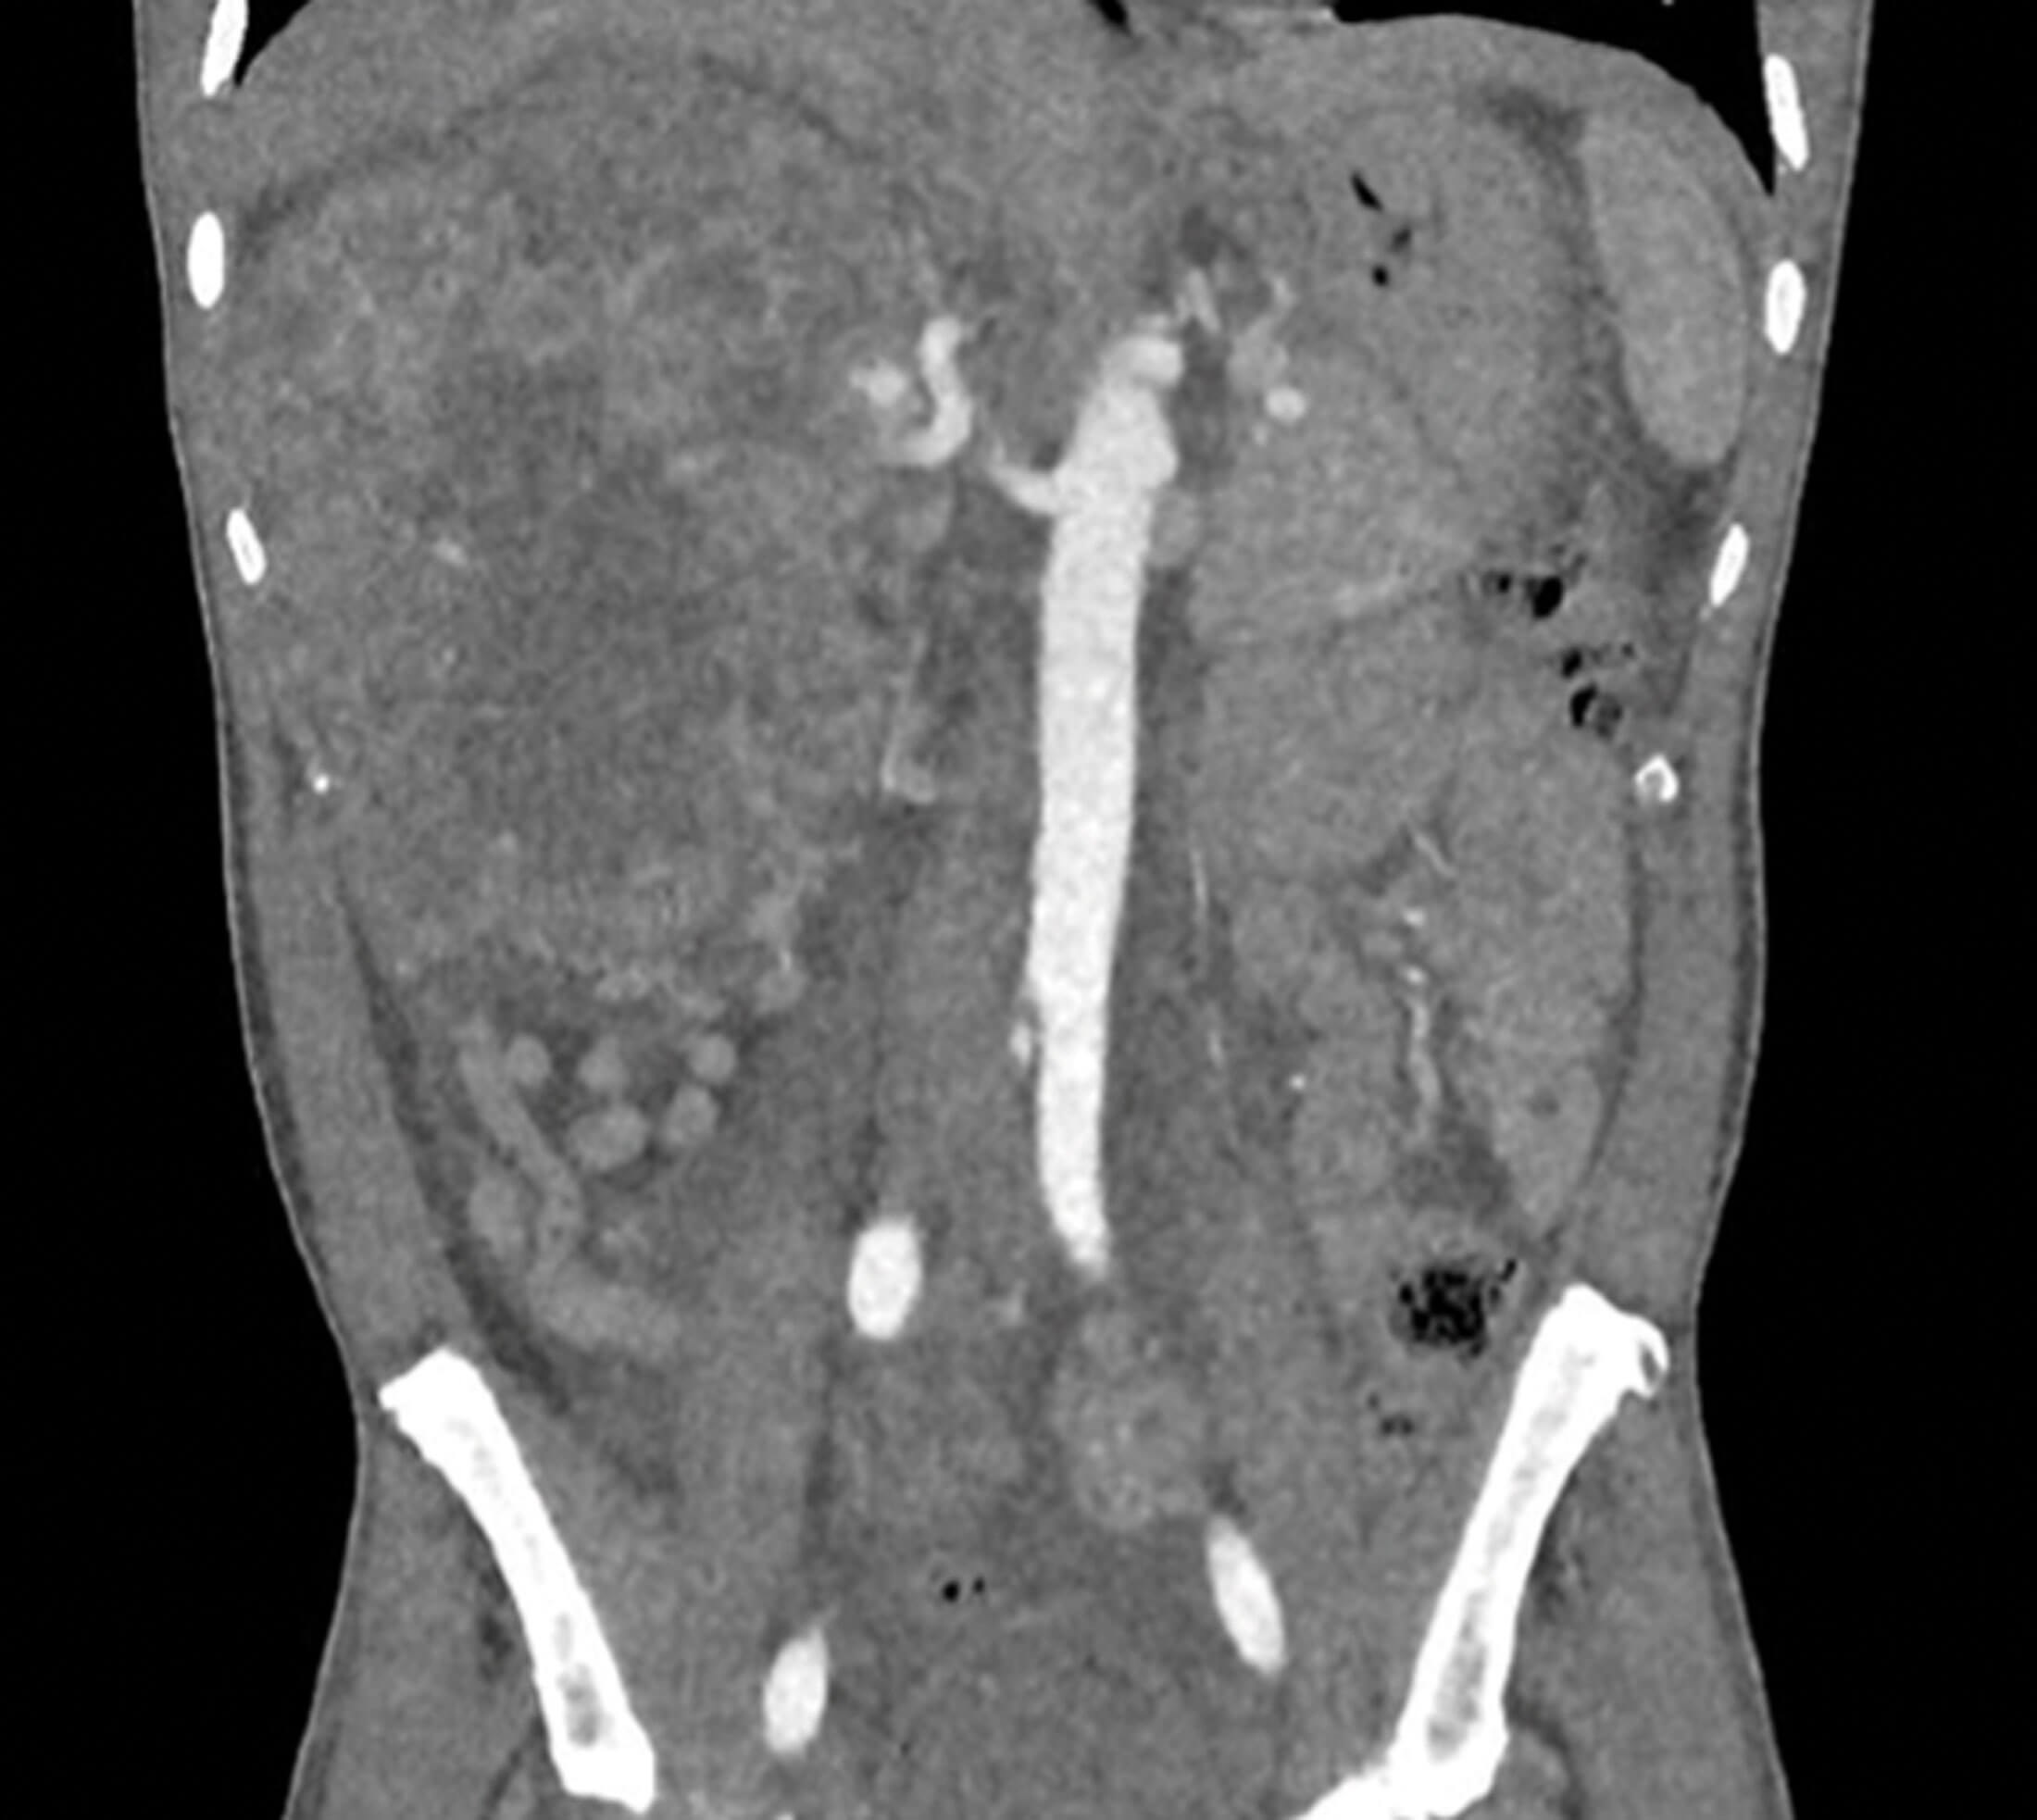

Figure 3.

1. Figure 3 is a coronal section of an arterial phase CT and demonstrates a large, heterogenous, solid, right tumour, which extends beyond Gerota’s fascia. Figure 4 is a coronal section of a thoracic CT demonstrating a left superior thoracic metastasis. These images demonstrate RCC with thoracic metastasis.